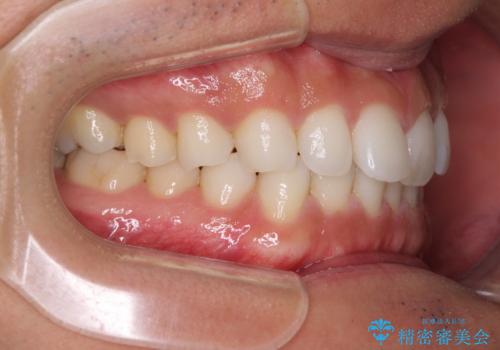

- 上下前歯のデコボコを気にして来院された患者様です。

以前矯正をした後戻りということで、歯列不正はそれほど大きくなかったため、インビザライン・ライトを用いて矯正治療を行うこととしました。

1日22時間以上しっかりと装着してくださったので、半年かからずに治療を終えることができました。